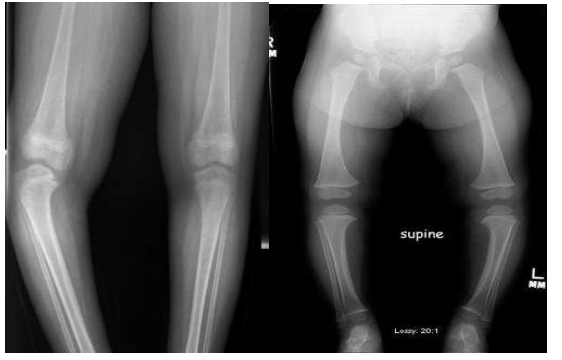

Gối vẹo trong (chân chữ O) và xoắn vặn xương chày vào trong là bình thường ở trẻ mới sinh và trẻ nhũ nhi, và vẹo tối đa vào 6-12 tháng tuổi.

Với sự phát triển bình thường, hai chân dần dần thẳng lại với góc chày đùi trung tính (thẳng trục) khi trẻ được 18-24 tháng (khi trẻ bắt đầu đứng và đi).

Sau đó, gối dần dần chuyển thành vẹo ngoài (chân chữ X). Biến dạng vẹo ngoài này đạt cực đại vào khoảng 3-4 tuổi với góc chày đùi ra ngoài trung bình là 12 độ.

Chân chữ O sau 2 tuổi được xem là bất thường. Nguyên nhân có thể do chân chữ O sinh lý nặng (nguyên nhân thường gặp nhất), một tình trạng bệnh lý, hoặc một rối loạn phát triển.

– Xác định tính đối xứng: ở vẹo trong sinh lý và bẩm sinh thường là hai bên và đối xứng, trong khi ở bệnh Blount có thể một hoặc hai bên, và khi bị hai bên thì thường không đối xứng.

– Xác định vị trí gập góc. Trong gối vẹo trong sinh lý thì có đường cong nhẹ ảnh hưởng cả đùi đến cẳng chân (cong vòng). Trường hợp lỏng dây chằng ngoài gối thì góc tại khớp gối. Trong bệnh Blount thường gập góc ở đầu trên xương chày (góc rõ ngay dưới gối). Trong xương chày vẹo trong di truyền gia đình thì góc ở thấp hơn (chỗ nối 1/3 giữa và 1/3 dưới. Hiếm khi gập góc chỉ ở đầu dưới xương đùi.

Hình ảnh học:

Xem xét chụp X quang (thẳng và nghiêng từ háng đến cổ chân) khi

- Trẻ >3 tuổi và biến dạng vẹo trong không cải thiện hoặc nặng hơn,

- Vẹo trong một bên hoặc không đối xứng

- Vị trí góc vẹo trong nhọn ở sụn tăng trưởng đầu trên xương chày, ngay dưới khớp gối

- Nghi ngờ bệnh lý khi khám lâm sàng, như thể tạng nhỏ (loạn sản xương), tiền sử chấn thương hoặc nhiễm trùng (não mô cầu), xương chày ngắn và xương mác dài tương đối, và tiền sử nhiễm độc kim loại.

Đo góc trục đầu trên xương chày- thân xương chày. Trong gối vẹo trong sinh lý góc này nhỏ hơn 11 độ, trong khi ở xương chày vẹo trong (Blount) góc này lớn hơn 11 độ.